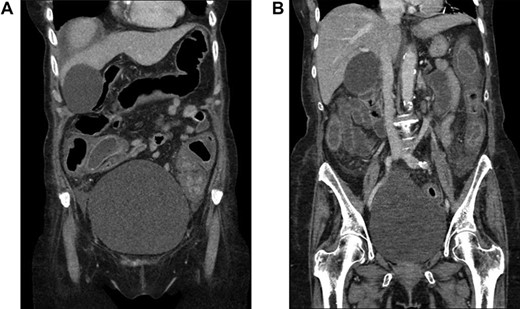

CT scan of the abdomen and pelvis demonstrating pancolitis from CDI.

A 75-year-old female presented to the hospital exactly 1 month following a prior hospital admission in which methicillin-resistant Staphylococcus aureus pneumonia was diagnosed and treated with IV vancomycin for 9 days. Four days prior to readmission, she was diagnosed with CDI and had symptoms of fever, nausea, vomiting and diarrhea. Her WBC was 22 860 cells per cubic millimeter (CCM) of blood, and PO vancomycin and IV metronidazole were initiated upon admission. At that time, a CT scan of the abdomen and pelvis was obtained and showed severe pancolitis consistent with CDI (Figure 1). Within 2 days, she became increasingly hemodynamically unstable with a leukocytosis of 38 680 cells per CCM. Due to severe CDI on appropriate medical therapy, surgical intervention was deemed necessary.